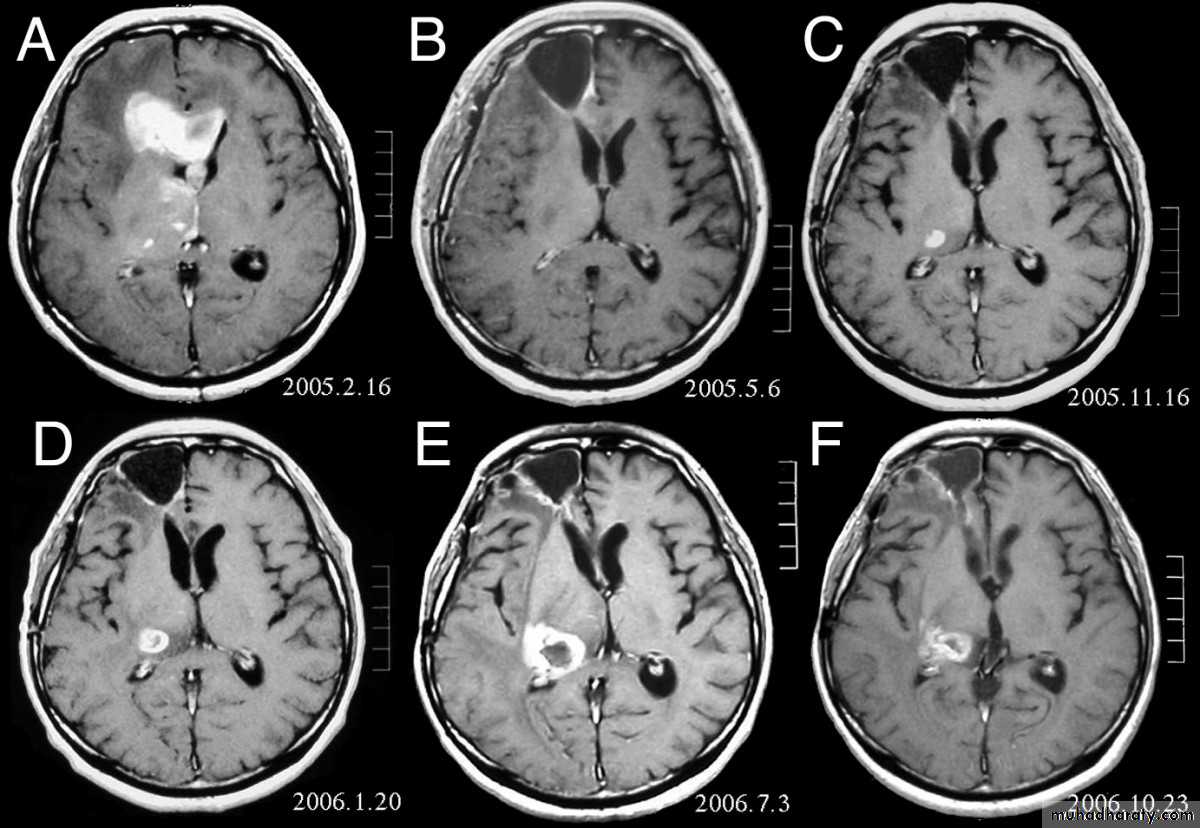

Glioblastoma multiformis:

The most malignant brain tumor, rapidly growing , red in color, highly vascular mainly affecting the cerebrum , some pathologists classify it as astrocytoma grade IV.Medulloblastoma:

arise from the epidermal lining of the ventricular system, usually whitish in color & can lead to early hydrocephalusCT scan of all gliomas shows usually hyperdense lesion, irregular in shape, surrounded by edema & may be enhanced with or without cystic degeneration.

Note: all gliomas are dealt with by surgical intervention ,by excision of the tumor followed by radiotherapy , but prognosis is not very good & fluctuates from 5 years survival of less than 5% in Glioblastoma multiformis to up to 100% 5 years survival in Oligodendroglioma treated by surgery & successive radiotherapy.